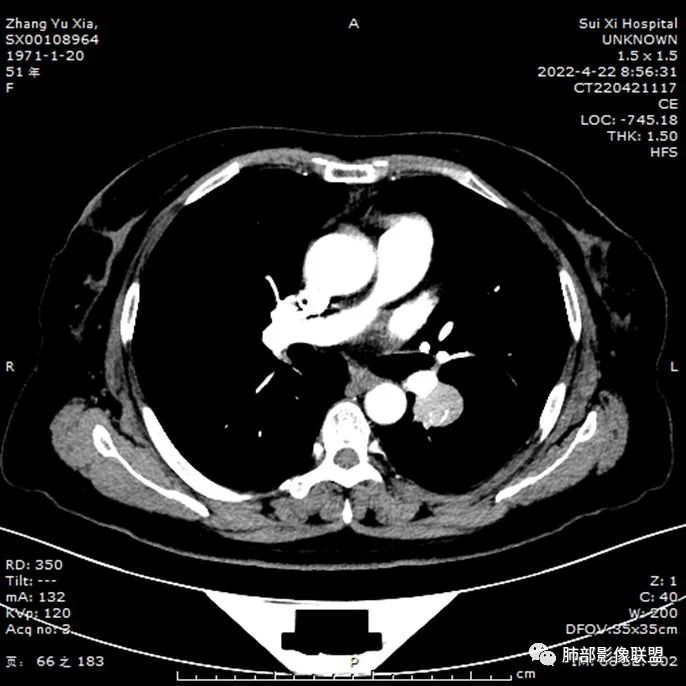

有钙化,也有血管进入,走形不正常

边缘有气体潴留

强化比较明显

内部有钙化

常规考虑良性